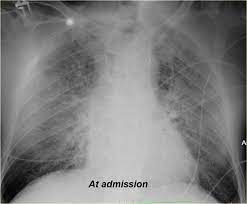

Peripartum Cardiomyopathy Circulation

Peripartum Cardiomyopathy Circulation from www.ahajournals.org